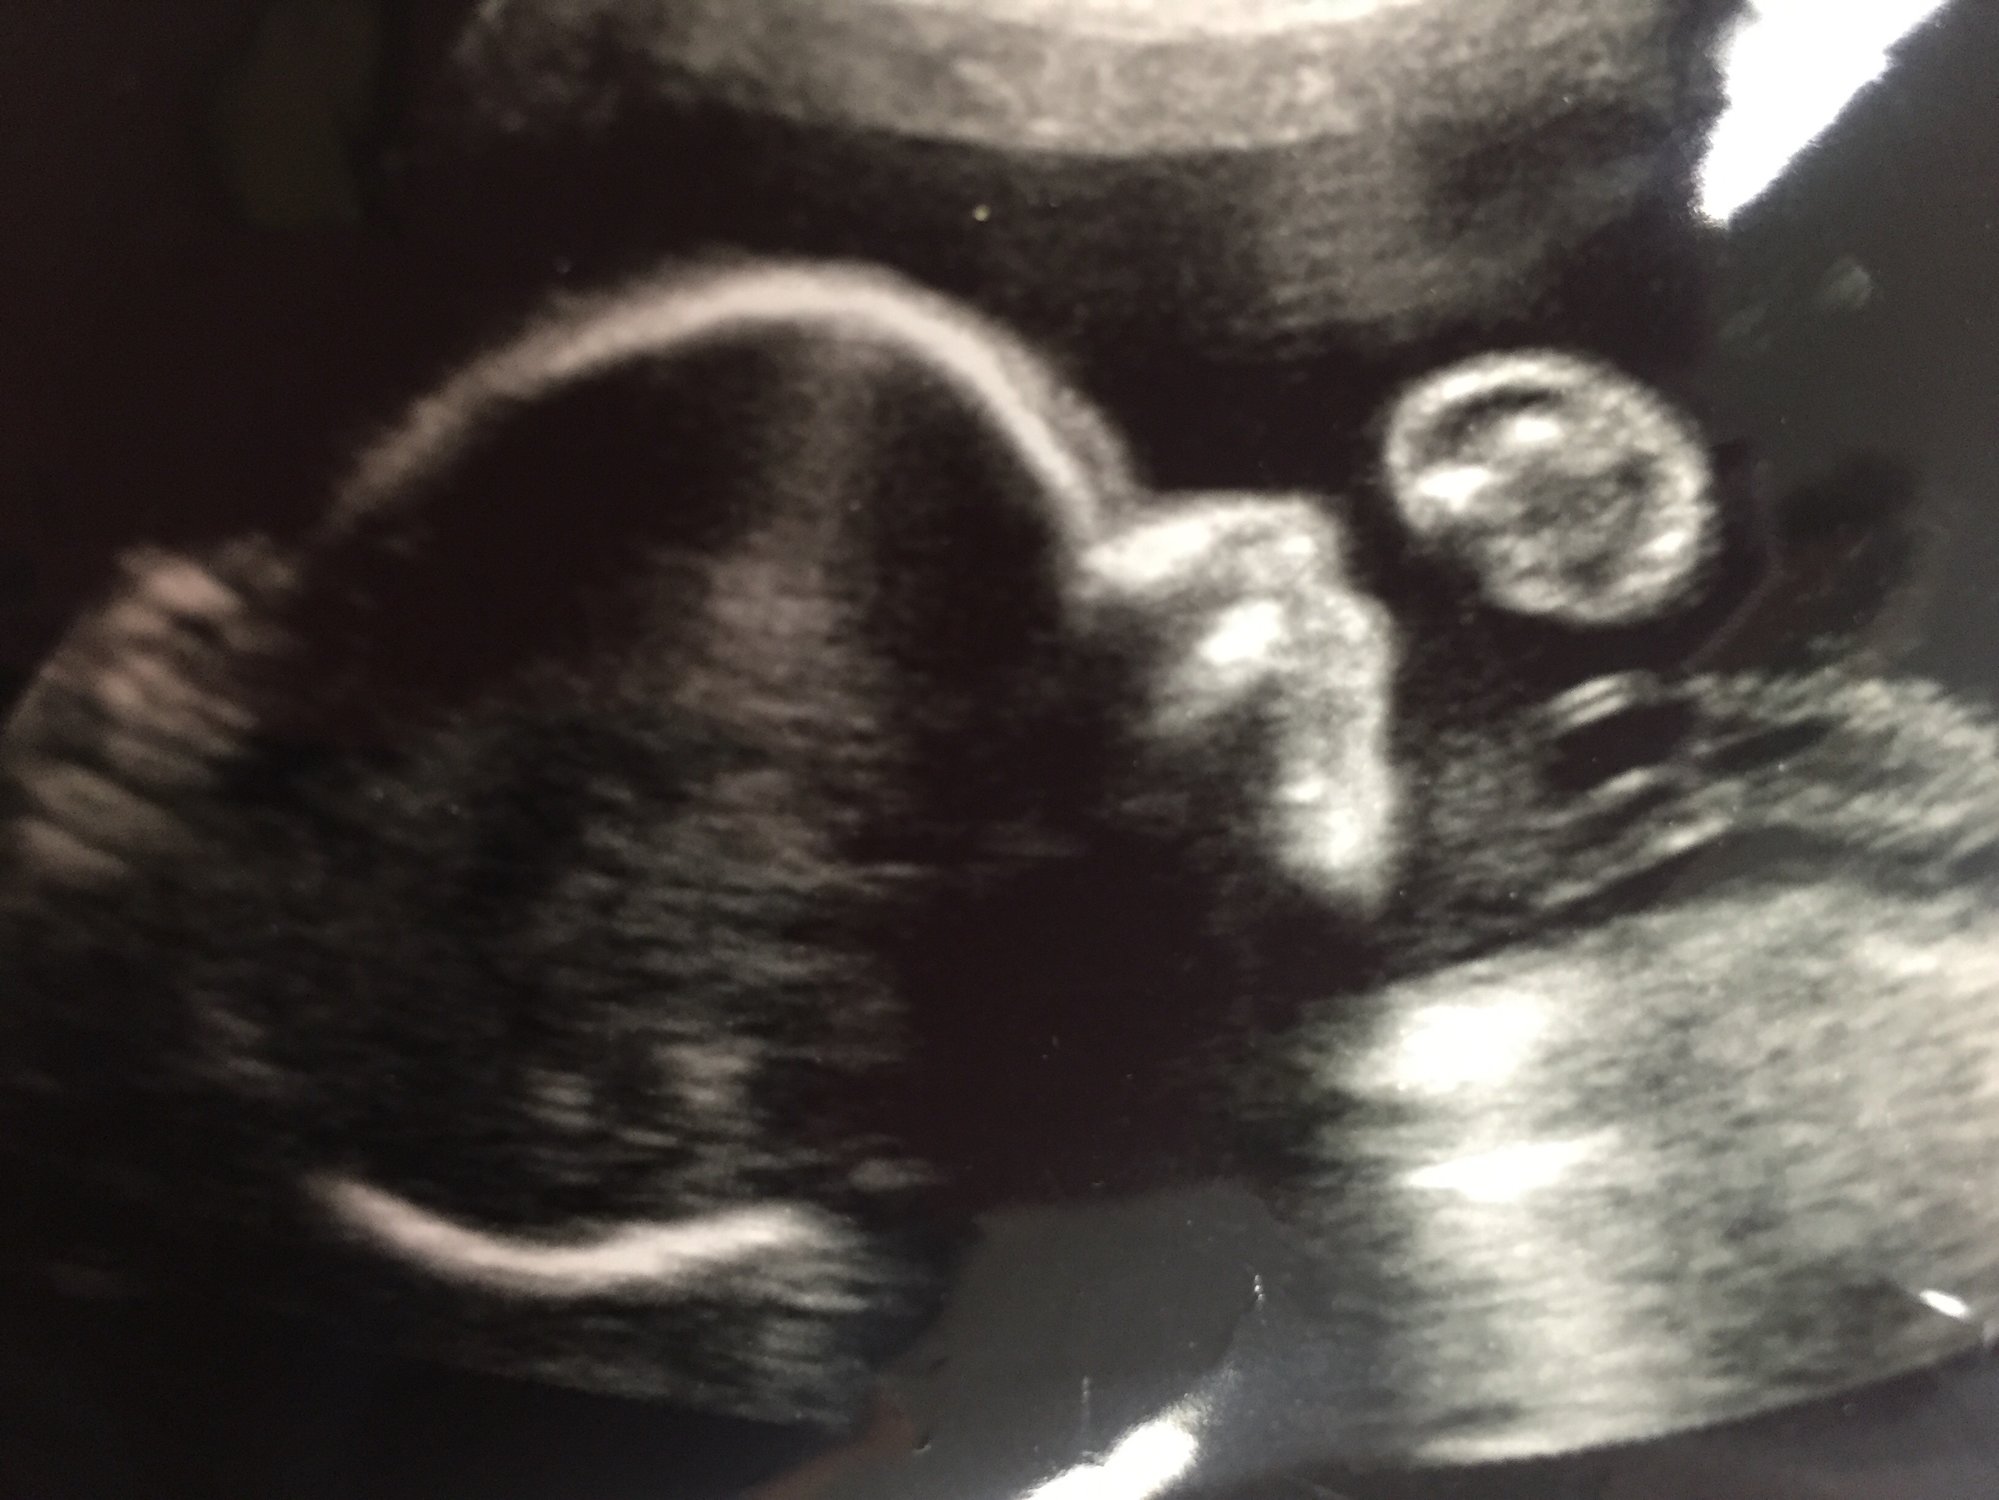

Our precious baby girl at 12 wks. Heartbeat 165 bpm